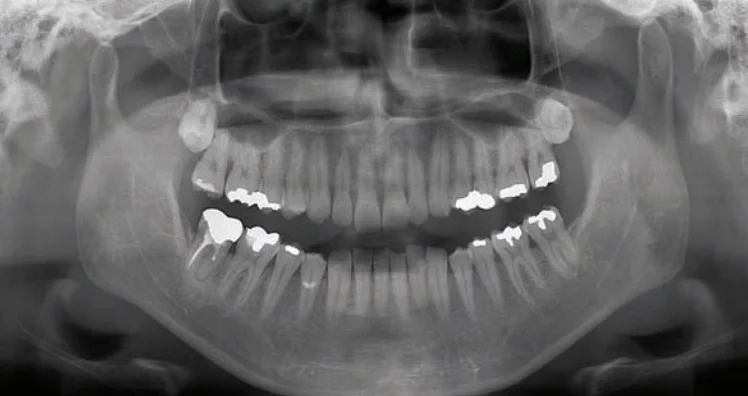

Panoramic Digital X-Ray (OPG)

This low radiation x-ray allows us to take a full panoramic digital image of the entire mouth and jaw area. It is useful for detecting wisdom teeth growth patterns, jaw joint (TMJ) abnormalities and problems within the supporting bone structures.